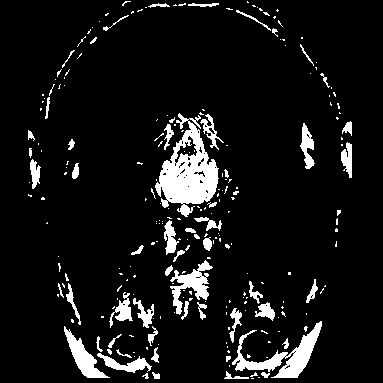

Creo que hay algo sobre una imagen que se generó teniendo cerebro 'rodajas' se imprime en rebanadas - jaja pero en plástico y no cerebro (aunque sería más fácil estudiar!).